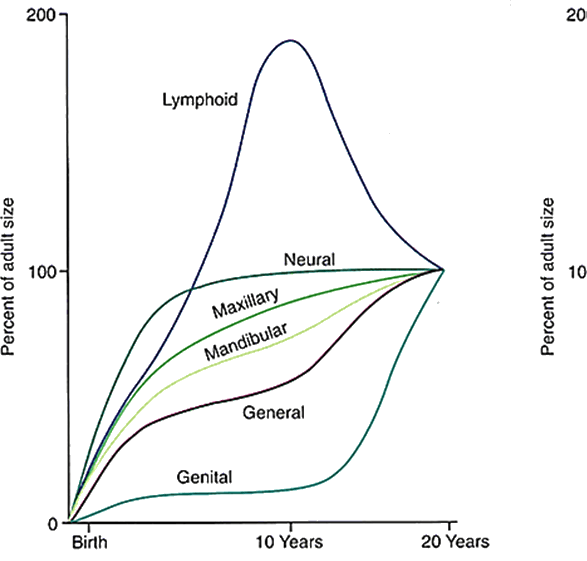

The Cephalocaudal gradient of growth follows a trend from the brain down: the further away from the brain, the later and longer it grows (in general). A fetus’ head takes up 50% of the total body length. By birth, it’s 30%, in adults about 12%. Different parts of the body grow and accelerate at different periods (See Scammon’s growth curve). There are generalized differences for the sexes, and great individual variation. Predicting growth spurts for certain areas (e.g. maxilla, mandible) is advantageous for orthodontists.

Mandibular growth usually follows the pubertal growth spurt. Because of the individual variation, chronological age is not a good predictor of mandibular growth. Neither is dental age (i.e. the eruption of teeth). Mandibular growth generally does, however, correspond to the patient’s skeletal age/development.